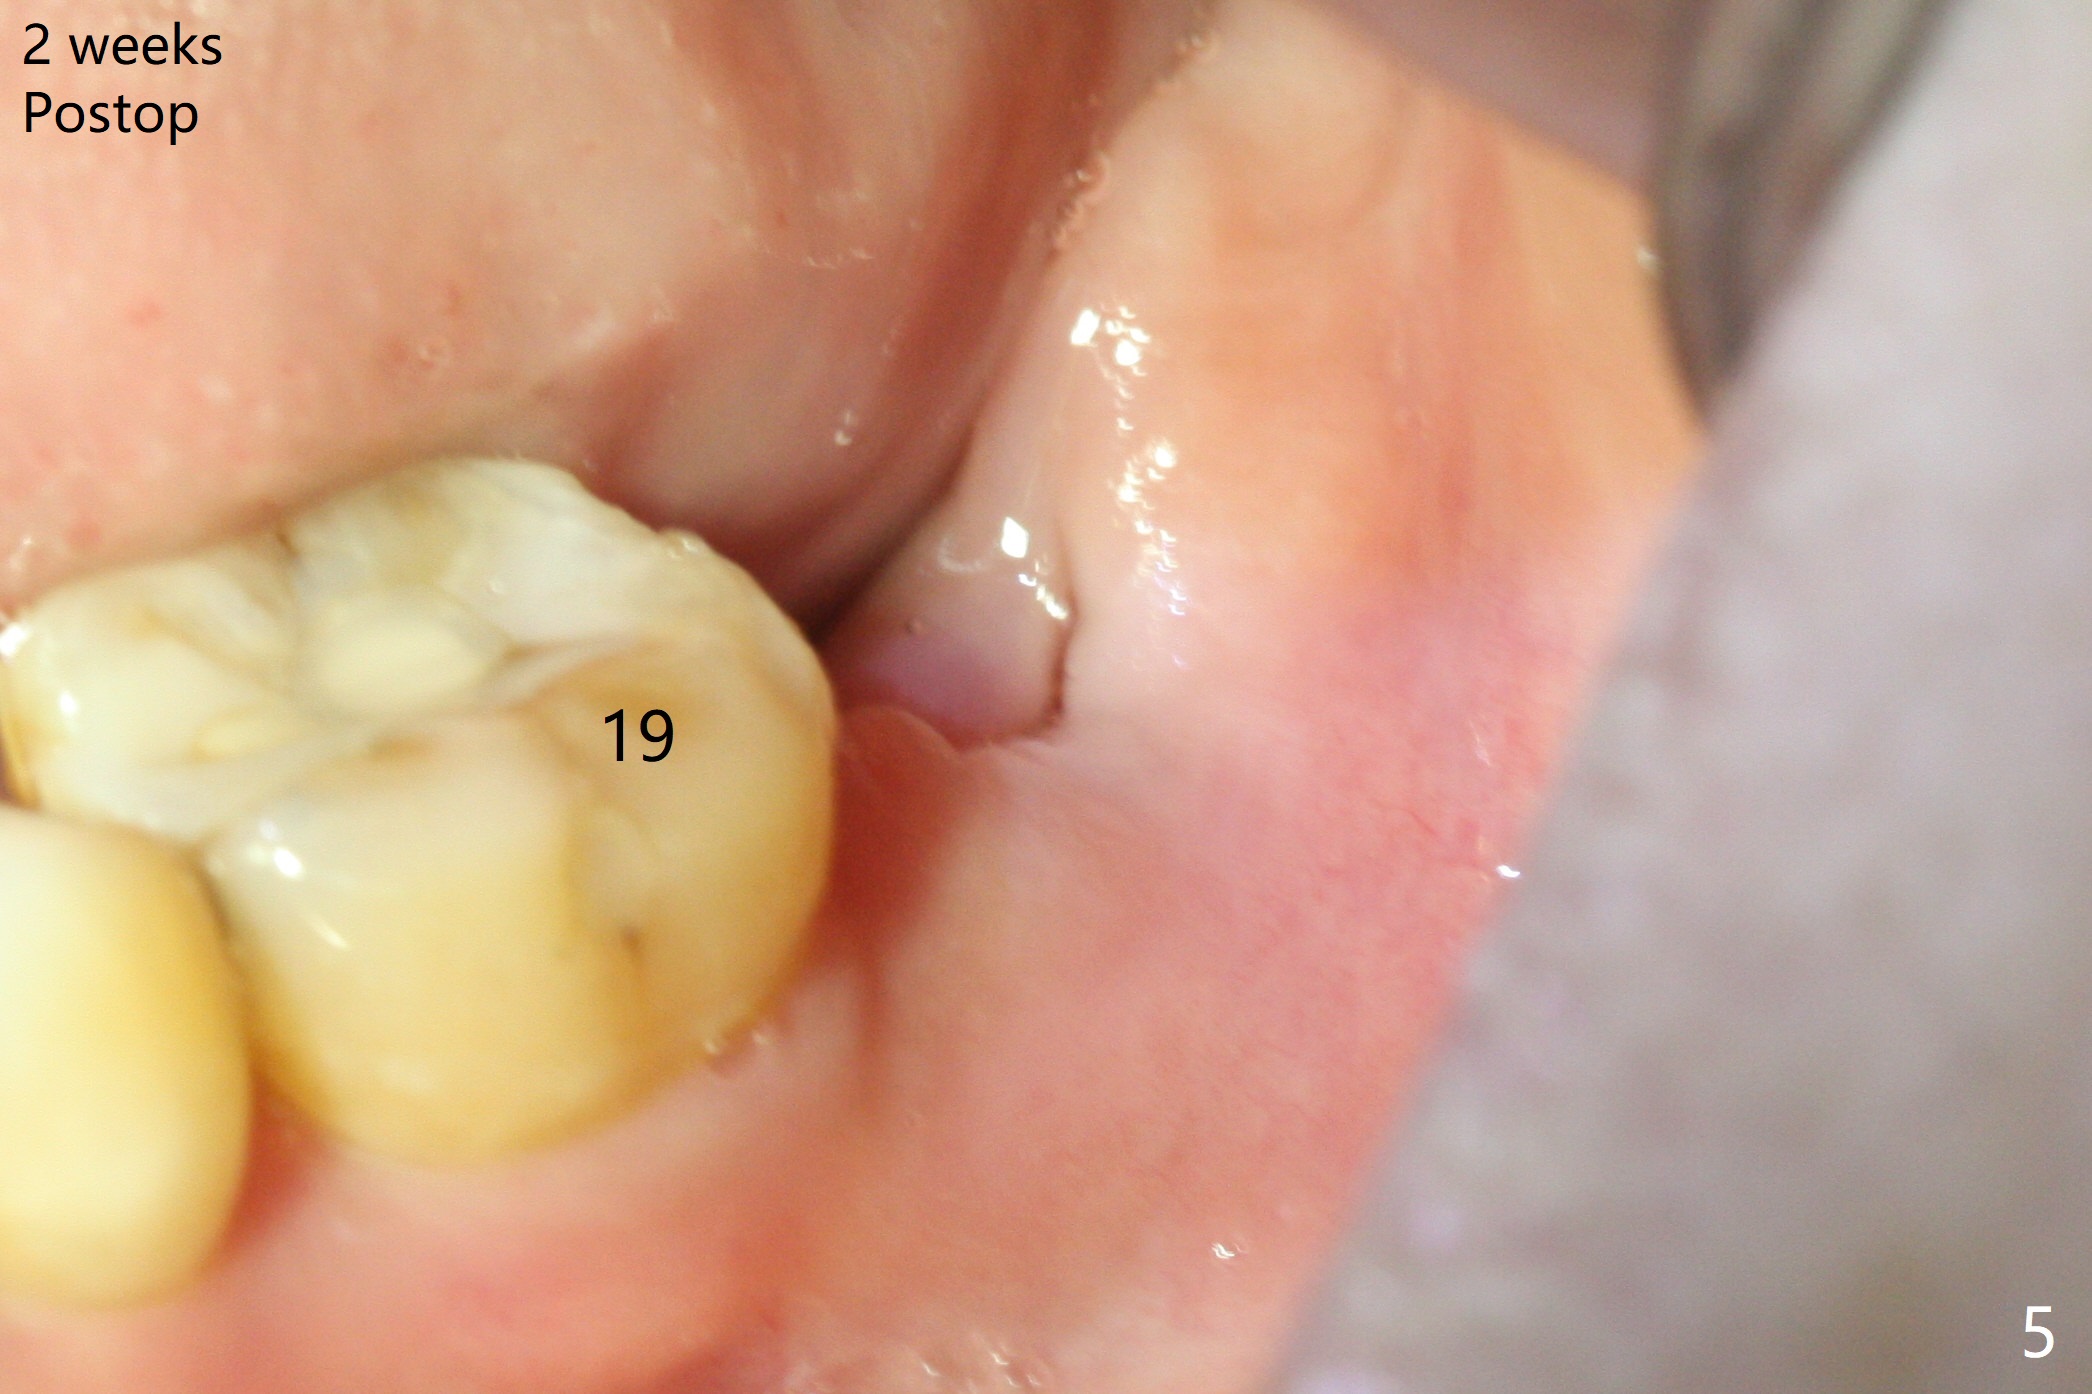

If the patient were not nervous and every step were followed by X-ray, light osteotomy in the bottom of the socket (flattening) may increase primary stability. A larger implant (9 or 10 mm) is a solution. The socket heals with disappearance of the fistula 2 weeks postop (Fig.5,6), but the ridge seems to have been reduced in width. The patient return for follow up 4 months postop; bone graft appears to remain in the socket (Fig.7). The ridge is apparently reduced further (data not shown). The patient prefers to have implant placement 1 month later. Take photos of the ridge buccally when the patient returns. In fact the patient agrees to have guided surgery. She postpones the surgery due to sickness for one more month. Implant placement will occur 6 months post extraction. The bone density should be higher than earlier.